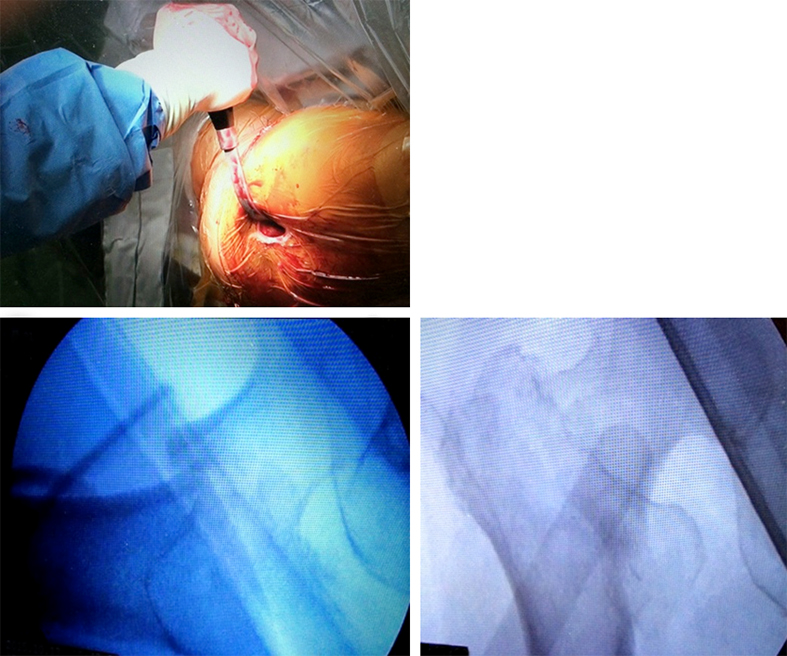

Curved elevator and L-shaped elevator

Reduction in certain proximal femoral nailing cases still remains a clinical challenge. Surgeons from Japan especially emphasize the importance of anatomical reduction of the medial and anterior cortices to improve the stability of the fracture and the efficacy of the nail. With no bone support at the medial and anterior cortices there is a higher risk for shortening of the femoral neck and fixation failure.

Because of the need for dedicated reduction instruments to facilitate the required reduction maneuvers, two new instruments have been developed: the curved elevator (Fig 7) and the L-shaped elevator (Fig 8).

The curved elevator is intended to align shifted fragments in the proximal femur through a lateral or an anterior approach (Fig 9). The recommendation is to obtain an extramedullary type of reduction with good bone support.

The L-shaped elevator is radiolucent. This elevator is usually applied for the reduction of strong anteversion in the lateral view (Fig 10).